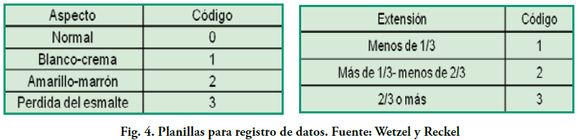

Al examen clínico las piezas presentan opacidades, delimitadas por esmalte normal, de color blanco-crema, amarillo o marrón (Figs. 1-4) que se diferencian de las presentadas por la lesión incipiente de caries, la amelogénesis imperfecta y la fluorosis endémica.

La coloración que presentan los defectos es indicador de severidad. Las lesiones pueden expresarse como una simple opacidad o disminución de translucidez, pasando por el color blanco, amarillo y amarronado. Estas últimas son consideradas las más severas, presentan mayor porosidad y ocupan todo el espesor del esmalte, mientras que las blanco cremosas son menos porosas localizándose en el interior del mismo(4).

Se clasificó la severidad de las lesiones por MIH según su aspecto: de color blanco crema, amarillo marrón y pérdida de esmalte (Fig. 6).